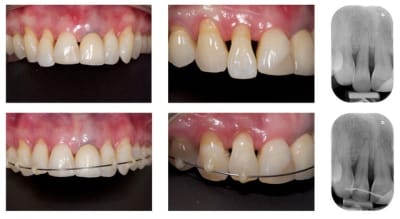

J'aimerais via un dispositif simple ingresser de 2 mm env. la 11. Idéalement a partir de la 21 avec une prov quand l'implant sera osteo-integrer ou via des mini implants ou un arc en dernier recours mais sans bracket.

Le support paro est stable depuis 3 ans et la maintenance parfaite. je pense ici qu'un traitement ortho serait une bonne solution. j'ai déjà effectué un traitement similaire sur une 12 égressé ( confère photo ci-joint) et même si comme certain l'ont décrit, on a quelques aléas a cette méthode, ca vaut le coup d'essayer.

Merci dancha d'intervenir, j'avoue que j’espérerai bien que ce cas te face sortir de ta tanière et tes conseils sur eugenol m'avaient bien aidé pour réaliser le traitement ci-dessous.

J'avais dans l'idée d'intégrer a ma futur prov sur 21 un dispositif d'ingression.